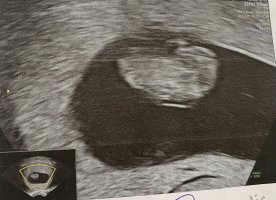

Skikkelig fint bildeVis vedlegget 382557

Dette var vel 7+5, hode, rumpe, arm og fot ses her. Ikke mye en se så tidlig, men vi var for å se etter hjerteslag og det fikk vi se.